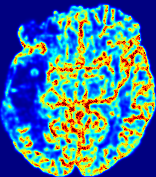

4.3.2 Diffusion Imaging via Advection-Diffusion

Slice #1Slice #2Slice #3Slice #4Slice #5Slice #6Dgtsuperscript𝐷gtD^{\text{gt}}Refer to captionRefer to captionRefer to captionRefer to captionRefer to captionRefer to captionDestsuperscript𝐷estD^{\text{est}}Refer to captionRefer to captionRefer to captionRefer to captionRefer to captionRefer to captionRefer to caption0.300.300.300.240.240.240.180.180.180.120.120.120.060.060.060.000.000.00(mm2/s)𝑚superscript𝑚2𝑠(mm^{2}/s)𝐕est𝟐subscriptnormsuperscript𝐕est2\|\bf{V}^{\text{est}}\|_{2}Refer to captionRefer to captionRefer to captionRefer to captionRefer to captionRefer to captionRefer to caption0.00300.00300.00300.00240.00240.00240.00180.00180.00180.00120.00120.00120.00060.00060.00060.00000.00000.0000(mm/s)𝑚𝑚𝑠(mm/s)

Figure 15: PIANO identifiability testing: diffusion imaging via advection-diffusion. Top row shows Dgtsuperscript𝐷gtD^{\text{gt}} used for simulating ground truth pure diffusion. Rows below show the estimated Destsuperscript𝐷estD^{\text{est}} and 𝐕est2subscriptnormsuperscript𝐕est2\|{\bf{V}}^{\text{est}}\|_{2} on corresponding slices. Note that the plotted value scale for 𝐕est2subscriptnormsuperscript𝐕est2\|{\bf{V}}^{\text{est}}\|_{2} is 0.01 of that for Dgtsuperscript𝐷gtD^{\text{gt}} and Destsuperscript𝐷estD^{\text{est}}.

Similarly, we test the behavior of PIANO when estimating both advection and diffusion from a pure diffusion-driven process. The goal is to determine if PIANO is able to recognize that there is only diffusion governing the given concentration time-series. We use the same ‘Diffusion Imaging’ data simulation of Sec. 4.2.1 as the concentration dataset, PIANO estimates both velocity 𝐕estsuperscript𝐕est{\bf{V}}^{\text{est}} and diffusivity Destsuperscript𝐷estD^{\text{est}}. Estimation results in Fig. 15 confirm PIANO’s identifiability again: the estimated 𝐕est2subscriptnormsuperscript𝐕est2\|{\bf{V}}^{\text{est}}\|_{2} is almost invisible compared to Destsuperscript𝐷estD^{\text{est}}, even plotted with a 1%percent11\% value range compared to that for Destsuperscript𝐷estD^{\text{est}}. On the other hand, Destsuperscript𝐷estD^{\text{est}} achieves comparable estimation performance as ‘Diffusion Imaging via Diffusion’ in which PIANO predicts Destsuperscript𝐷estD^{\text{est}} alone (shown in Fig. 13).